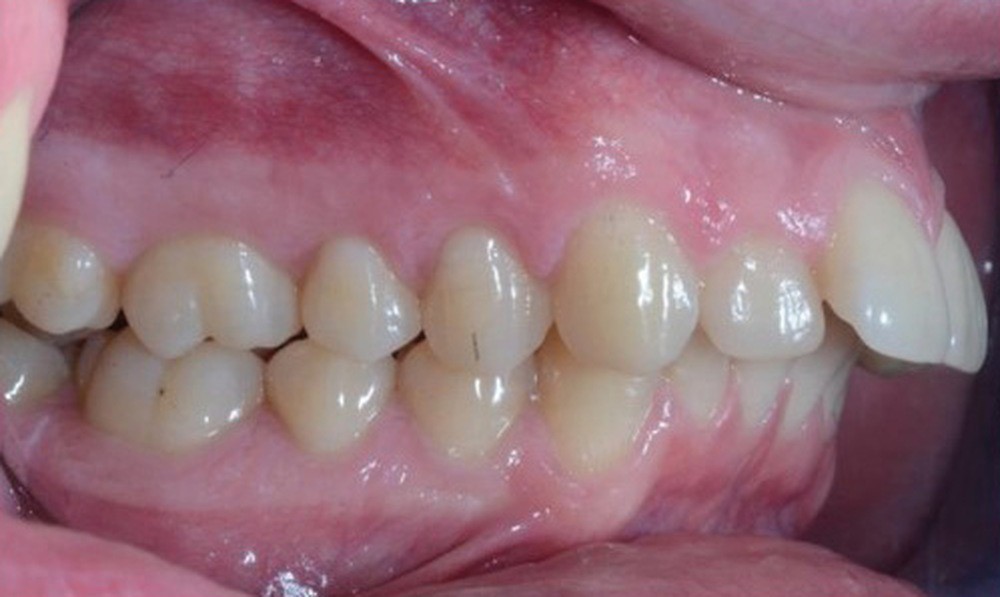

C’est à ces questions que nous permettront de répondre les deux premiers conférenciers, parodontologistes : le Dr Béatrice Straub nous présentera le renfort parodontal minéralisé, technique qu’elle a développée et pratique depuis de nombreuses années, pour éviter les préjudices des mouvements orthodontiques à risque, notamment lors des décompensations préchirurgicales (fig. 1a-d) ; le Pr Anton Sculean abordera le thème des greffes, avec leurs indications, les différentes techniques à privilégier et illustrera ses propos par de nombreux cas cliniques aux résultats esthétiques impressionnants.